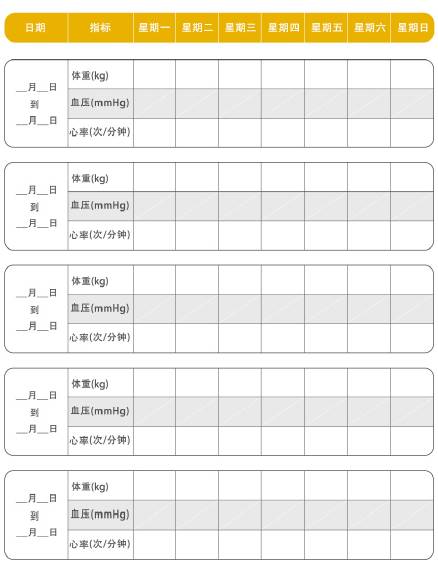

戒烟戒酒,低脂清淡饮食,肥胖的患者要适当减重。还应少食多餐,因为饱餐可诱发或加重心衰;注意适度的休息和运动,多与家人朋友沟通排除焦虑和孤独等负面情绪;同时还应该学会自我监测:填写日常管理记录表,每天检查脚踝、腿有没有水肿,注意不要过度运动,避免感染等。

日常管理记录表